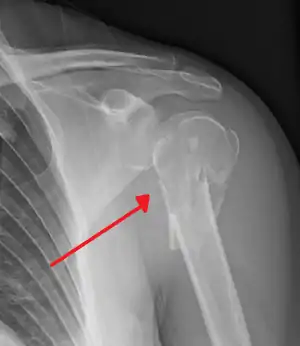

| Multi-fragmented fracture of the proximal humerus with involvement of the greater tuberosity | |